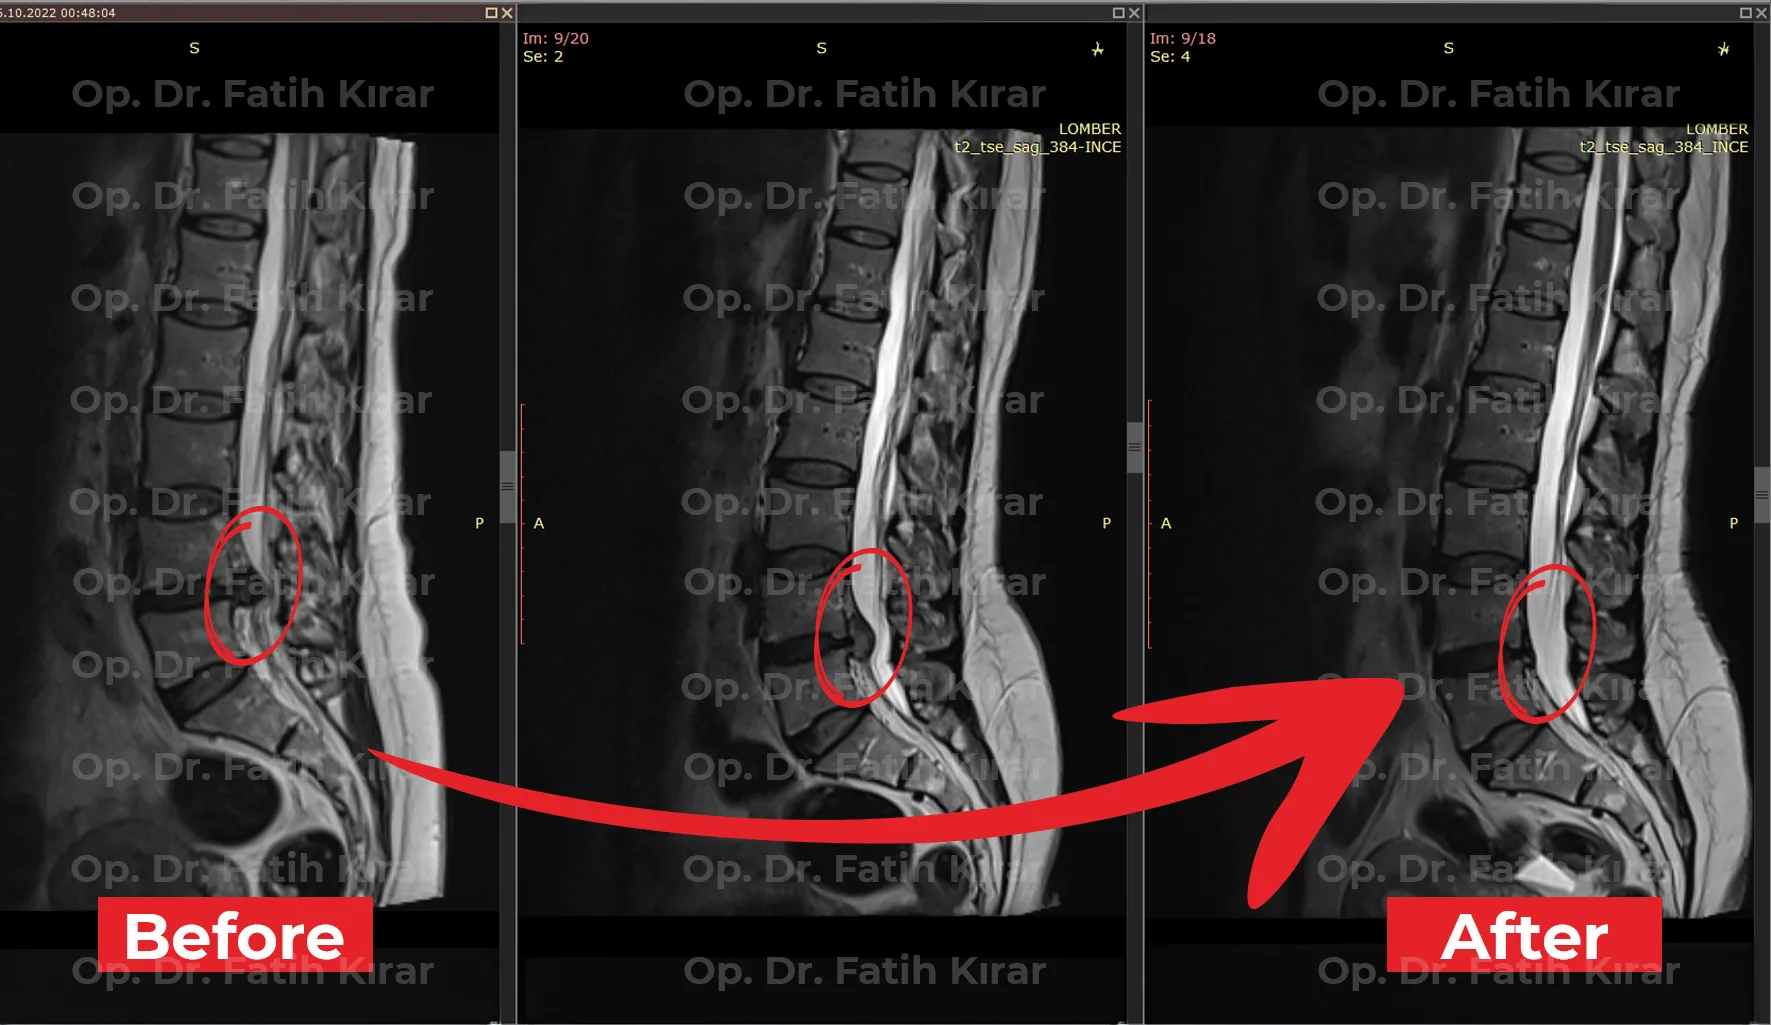

Clinical Results

MRI Images

Before and after treatment MRI images of our real patients